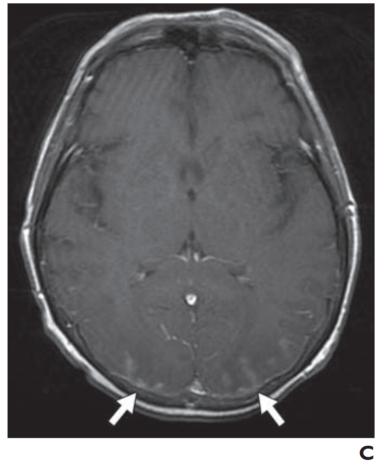

MRI 也可用于急性卒中,尽管技术和人员要求限制了它在许多中心的应用。DWI 是检测超急性梗塞(出现后 < 30 分钟)最敏感的序列,先于 CT(6 小时)和 T2 加权成像(6-12 小时)识别病情变化。急性梗塞中的扩散受限分别对应于 DWI 和 ADC 图上信号增加和减少的区域。随着梗死发展为亚急性和慢性阶段,会发展为血管源性水肿和脑软化症。这反映在 T2/FLAIR 信号强度的逐渐增加,且伴随着扩散系数的正常化(图3A ), 3B, 和3C)。也可以进行3D-TOF MRA或者3D-ASL检查。然而,与 CT 相比,空间分辨率较差,图像容易出现运动、磁化率和流动伪影。

图 3A —患有线粒体脑肌病、乳酸性酸中毒和中风样发作 (MELAS) 的梗死患者的 MR 图像。T2 加权图像显示两个枕叶信号增加,右侧(粗箭头)大于左侧(细箭头)。

图 3B —患有线粒体脑肌病、乳酸性酸中毒和中风样发作 (MELAS) 的梗死患者的 MR 图像。弥散加权图像也显示双侧高信号,右侧(粗箭头)大于左侧(细箭头)。

图 3C —患有线粒体脑肌病、乳酸性酸中毒和中风样发作 (MELAS) 的梗死患者的 MR 图像。表观扩散系数图像(ADC)显示右侧信号减弱(粗箭头)但左侧信号正常(细箭头)。因此,右侧病变为急性梗死,弥散受限。左侧病变代表亚急性或慢性梗塞,弥散加权图像上有 T2 透过效应。